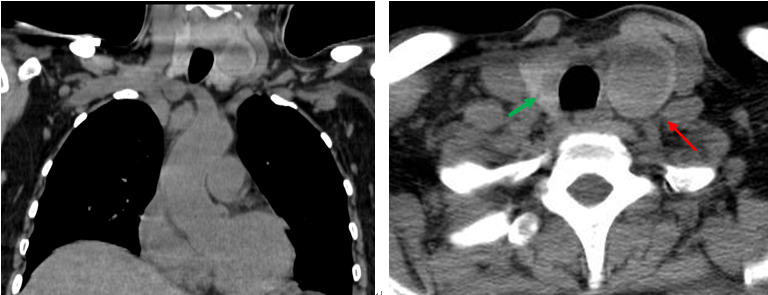

患者同期甲狀腺CT平掃檢查所見(jiàn):

甲狀腺形態(tài)增大,雙葉見(jiàn)類圓形低密度影,大小分別為2.4×2.9cm(左,紅箭),0.7×1.1cm(右,綠箭)。

本例患者懷疑“甲狀腺癌”,擬行手術(shù)治療,術(shù)前檢查發(fā)現(xiàn)血PTH升高,鈣磷代謝異常,臨床提示患者同時(shí)存在甲狀旁腺功能亢進(jìn),術(shù)前定位功能亢進(jìn)的甲狀旁腺腺體,能有效減少術(shù)中探查對(duì)患者帶來(lái)的創(chuàng)傷,縮短手術(shù)時(shí)間。在本例99mTc-MIBI雙時(shí)相顯像中,我們觀察到甲狀腺左葉中上部有一個(gè)異常放射性不均勻濃聚灶,提示為功能亢進(jìn)的甲狀旁腺,與患者同期甲狀腺CT檢查示囊實(shí)性結(jié)節(jié)吻合,術(shù)后病理證實(shí)為左側(cè)甲狀旁腺腺瘤,甲狀腺右側(cè)葉結(jié)節(jié)為甲狀腺乳頭狀癌。(錢紅?關(guān)祥禎)